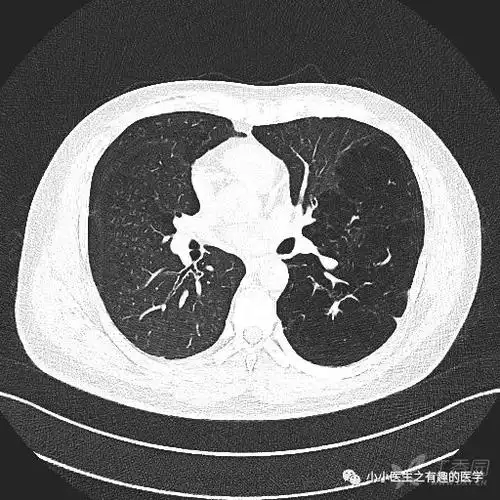

肺气肿ct典型图谱,一学就会_医学界-助力医生临床决策和职业成长

ct经典图谱:肺气肿拿不准?经典ct,3分钟学会